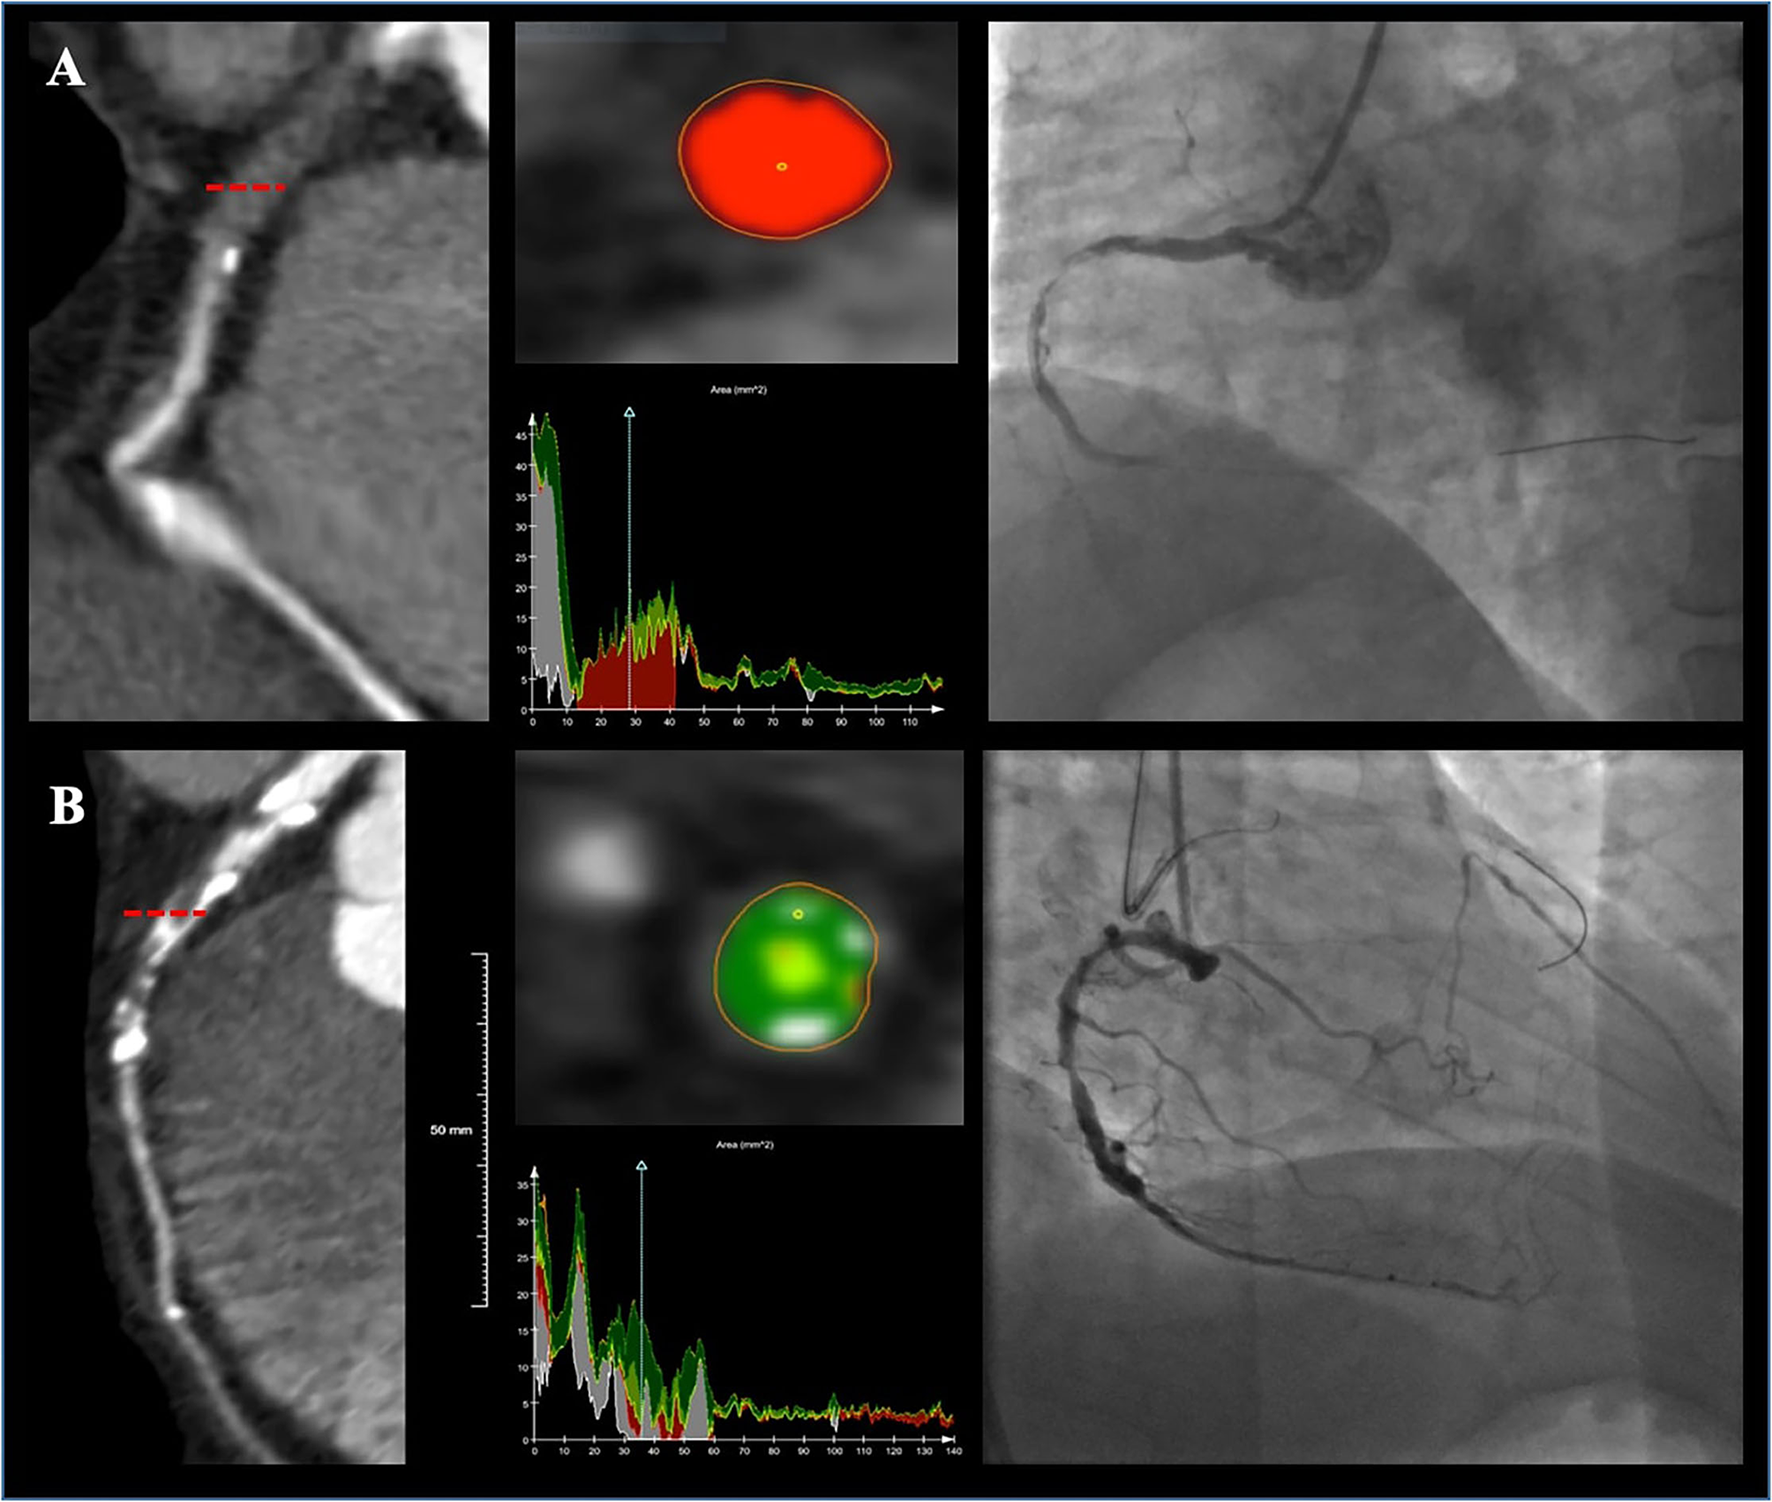

Figure 3

Two representative cases showing plaque compositions and guidewire (GW) crossing outcomes. Lesion (A) was a right coronary artery (RCA) lesion with soft CTO (80.7% necrotic core, 17.4% fibrous fatty, 1.6% fibrous, and 0% dense calcium) and the GW was successfully passed at 20 min. Lesion (B) was a left anterior descending artery (LAD) lesion with hard CTO (46.4% fibrous, 21.9% dense calcium, 17.8% fibrous fatty, and 13.5% necrotic core) and the GW was failed to be advanced cross the CTO.